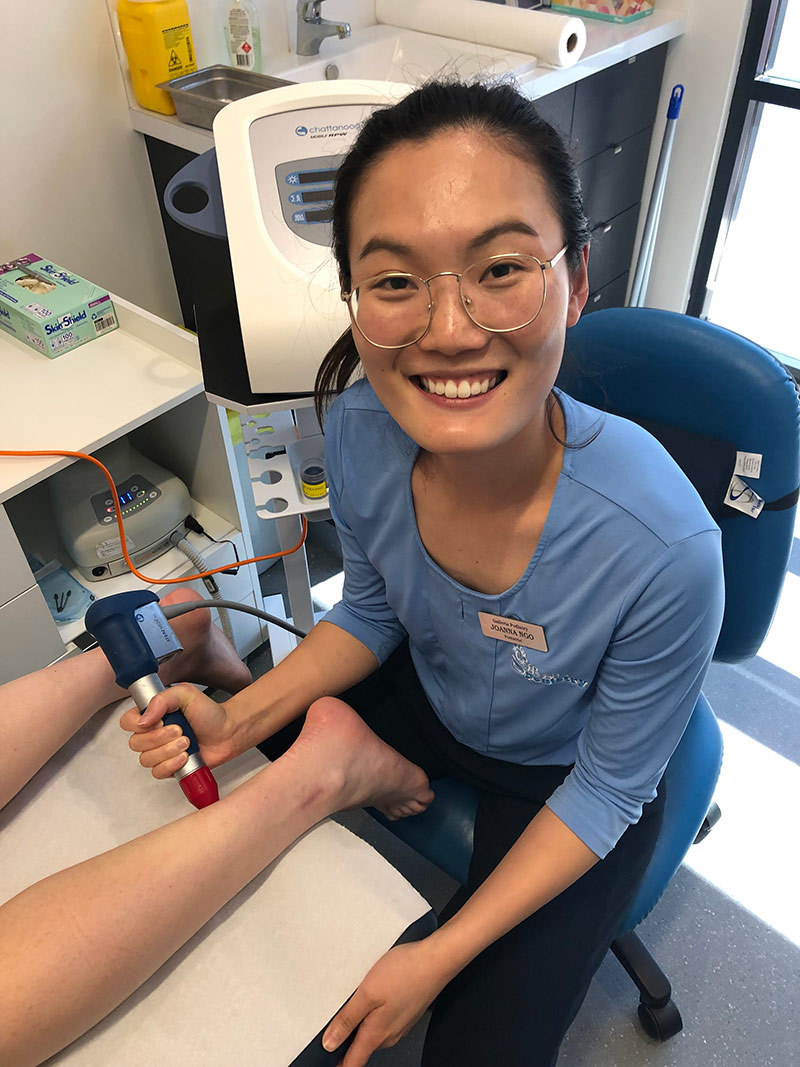

At Galleria Podiatry, our team of podiatrists understands how debilitating an injury or illness of the feet, ankles, knees or hips can be. We work to diagnose the source of your discomfort so we can help you get back on your feet.

All the podiatrists at Galleria Podiatry have graduated from the University of WA or Curtin University and all are members of the Australia Podiatry Association (WA).

- Technology – We provide the latest technology and state-of-the art equipment.